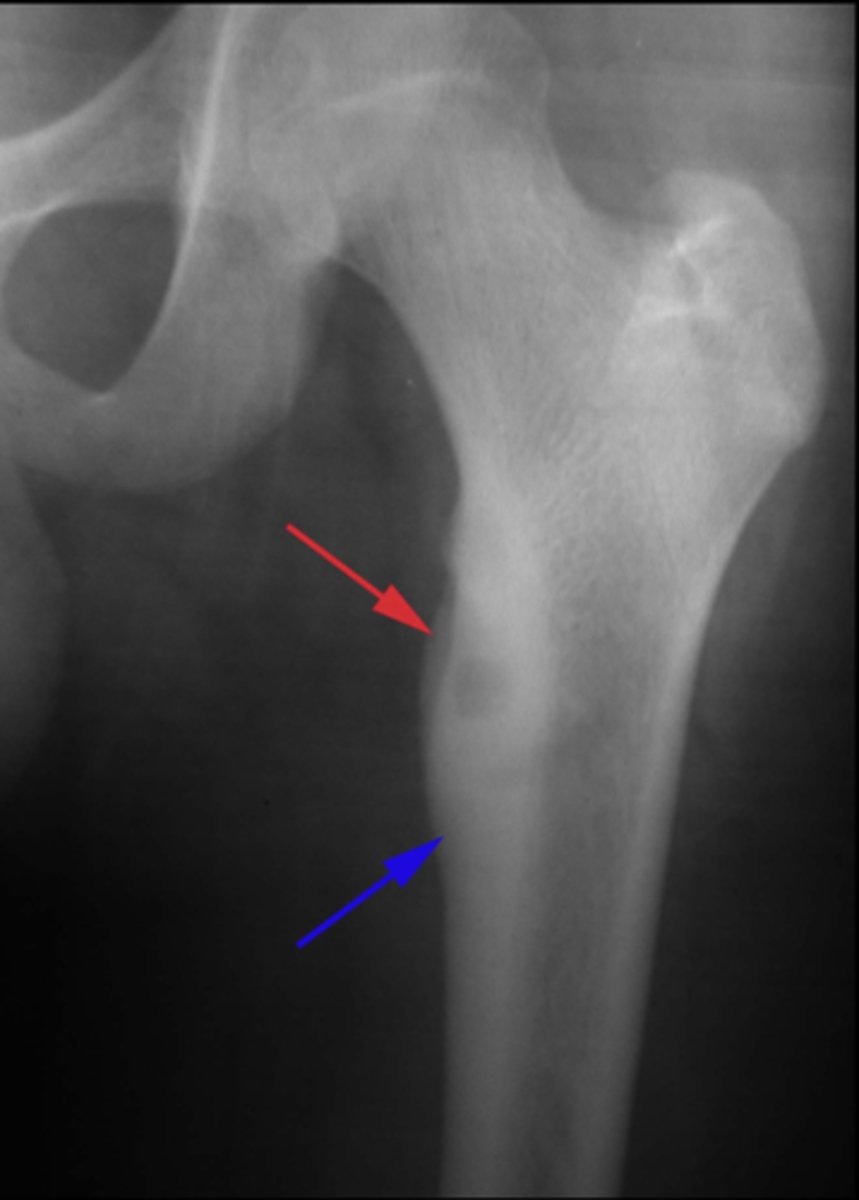

Geographic bone blister

ID radiographic feature of non-ossifying fibroma indicated by top arrow

Septations

ID radiographic feature of non-ossifying fibroma indicated by bottom arrow

Pathologic fracture

Non-ossifying fibroma with _____